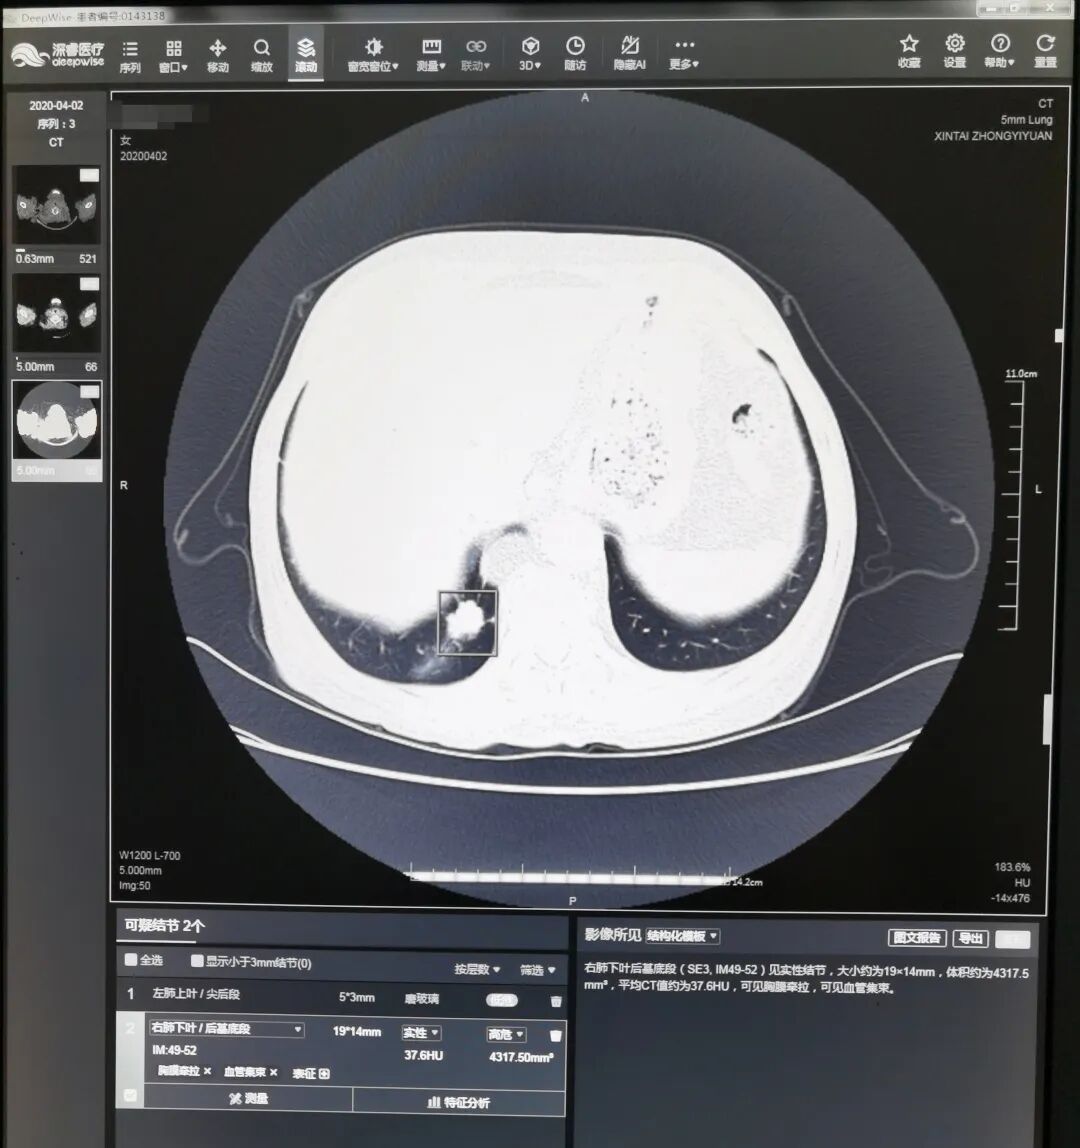

“人工智能(AI)系统可以对每一副图像进行地毯式筛查,避免因为经验差异和医生的视疲劳造成的漏诊。”李美介绍,传统人工筛查需要医生逐个区域用鼠标不停地拖曳、放大,用肉眼一点点甄别影像的每一处可疑部位,一般需要用时3—5分钟,有的疑难的影像片甚至需要更长时间。而人工智能肺小结节筛查系统,基于数十万份高质量胸部CT数据的神经网络深度学习、多维训练,相当于把数十万份由专家诊断的肺小结节大数据植入系统,作为强大支撑作出判断。借助人工智能的力量,系统即能快速对所有完成的胸部低剂量螺旋CT扫描图像进行筛查,并自动对可疑肺小结节进行精准定位,用色框清晰标注小结节坐标提示医生,并对结节的可疑病灶数、性质、直径、体积、CT值等信息以及影像学表现进行描述,医生就可以对这些有问题的地方着重处理。

如图显示,AI软件可以自动识别3mm以上的实性结节、磨玻璃结节(绿方框所示),省去医生寻找的时间

同时,人工智能还能对同一个患者前后做的CT影像检查数据进行对比和分析,不仅大大节省了医生的时间,更可以帮助医生对患者的结节生长速度和动态作出客观的判断,提高诊断的精准率,有助早期诊断和治疗。